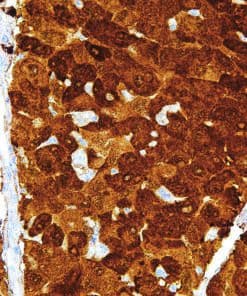

Thymidylate Synthase

Thymidylate Synthase (TS) is a crucial enzyme responsible for the synthesis of 2′-deoxythymidine-5′-monophosphate (dTMP) a precursor for thymidylate which is necessary for DNA replication and repair from 2′-deoxyuridine-5′-monophosphate (dUMP). In terms of cancer, TS is an important target for cancer treatment as the inhibition of TS and therefore nucleotide synthesis necessary for cell growth has shown to be a vital part for successful treatment against colorectal, pancreatic and breast cancers.

| Clone | IHC697 |

| Source | Mouse Monoclonal |

| Positive Control | Colon Cancer |

| Dilution Range | 1:100 – 1:400 |